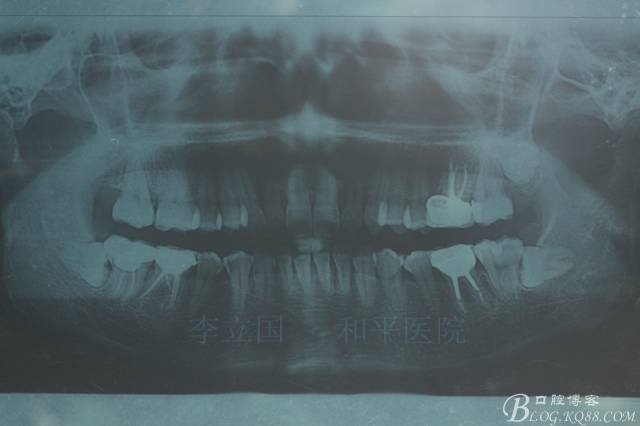

1.拔除14、24、31。

1.患者上前牙直立,面型前突,典型的嘴凸牙不吐,關(guān)鍵是前牙轉(zhuǎn)矩控制,建議使用高轉(zhuǎn)矩托槽。

2.磨牙關(guān)系一側(cè)完全遠(yuǎn)中,一側(cè)遠(yuǎn)中尖対尖,采用兩個(gè)上4,一個(gè)下1的拔牙模式。